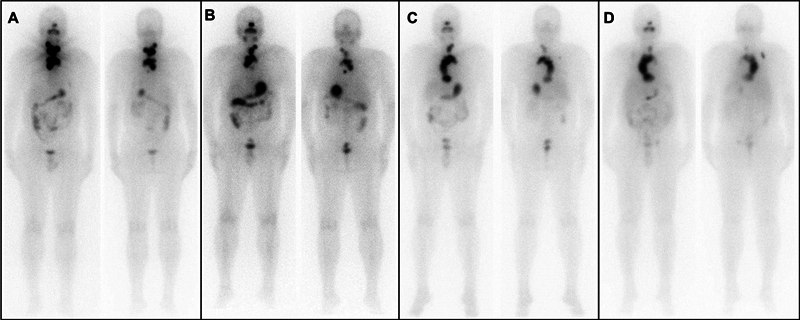

A unique case of papillary carcinoma of the thyroid with an extensive tumor thrombus extending into the right ventricle is presented. The patient was a known case of solid variant of papillary carcinoma of thyroid, post three cycles of radioiodine therapy, had reported for a diagnostic 131 I-NaI scintigraphy as a part of the workup for planning the next 131 I therapy. Clinically, the patient was asymptomatic. 131 I-NaI scintigraphy showed an arcuate pattern concentration of tracer in the upper mediastinum, which descended up to the lower mediastinum. A 131 I-NaI single photon emission computed tomography/computed tomography (SPECT/CT) showed a tracer avid tumor with an extensive tumor thrombus extending from the left brachiocephalic vein to the right ventricle. 18 F-fluorodeoxyglucose positron emission tomography/computed tomography ( 18 F-FDG-PET/CT) and magnetic resonance imaging (MRI) demonstrated similar findings. The patient was decided to be managed with tyrosine kinase inhibitors as surgical intervention was not deemed possible due to the involvement of major vessels and the high risk of bleeding.